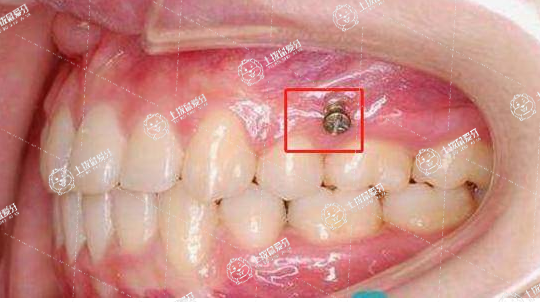

經常有矯正的朋友經常來問:醫(yī)生我要不要打骨釘?打骨釘疼不疼呀?能不能不打啊?”其實,骨釘在正畸過程中使用廣泛,是正畸醫(yī)生經常使用到的幾大法寶之一。矯正牙齒擁擠需要打骨釘嗎?對此,牙科醫(yī)生帶大家簡單來了解一下。

需要。在牙齒出現擁擠的時候進行矯正,可能會出現空隙不夠的情況,造成間隙被后面的牙齒替代,所以需要使用骨釘進行重新排列,幫助緩解擁擠的情況。但是如果牙齒擁擠不是很厲害,在矯正的過程中不會填滿空隙,可以允許后牙向前占用一部分空隙。而出現擁擠還伴有前突的癥狀時,最好使用骨針。骨針在矯正完全后,會被取出,不會對患者的口腔造成影響。

骨釘近幾年使用比較多,之前治療不用骨釘。牙齒特別擁擠時,因為前牙移動或者解除擁擠后間隙不夠,為防止間隙被后邊牙齒前移代替,所以醫(yī)生建議擁擠嚴重患者打骨釘,通過骨釘排齊前面牙齒,解除前牙擁擠。

骨釘也不是非常大問題,不用緊張,骨釘對患者本人沒有任何影響,牙齒解除擁擠排齊后,就會把骨釘取出來。